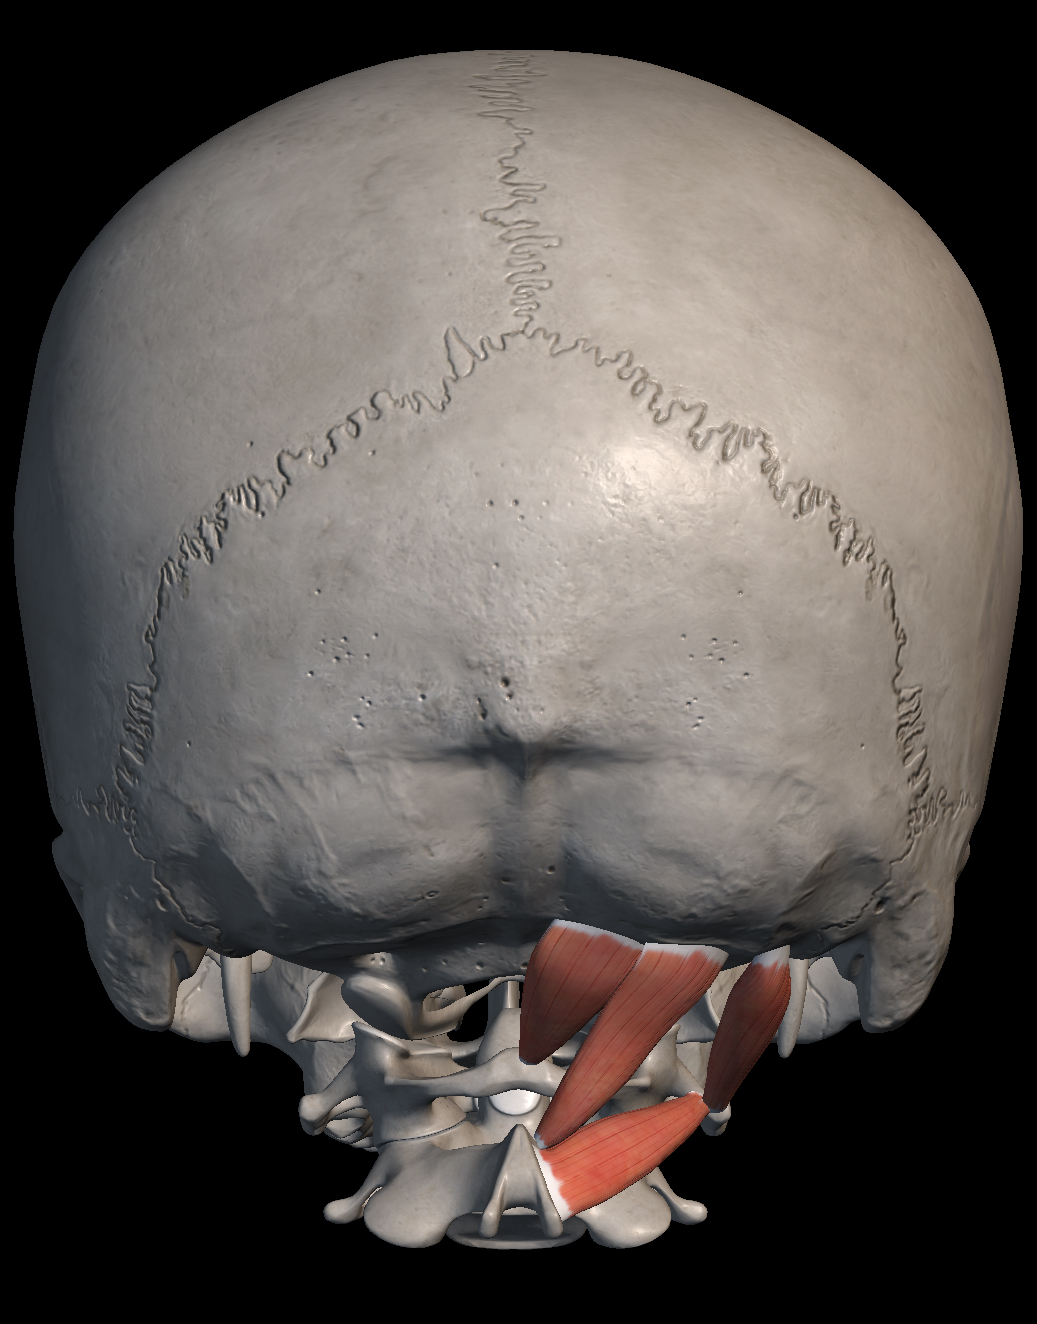

I muscoli sotto occipitali sono un insieme di quattro muscoli (otto in totale tra destra e sinistra) che collegano il sistema occipito-atlanto-assiale ovvero il sistema che mette in relazione l’occipite con le prime due vertebre cervicali (atlante c1 e epistrofeo c2). Questi muscoli sono il retto posteriore maggiore della testa, il retto posteriore minore della testa, l’obliquo superiore della testa e l’obliquo inferiore della testa. Questo sistema ha tantissime relazioni con varie strutture del corpo e una disfunzione di questo sistema potrebbe creare un disallineamento con vari tipi di disordini, sia posturali sia neurovegetativi. Per la sua importanza, questo sistema è uno dei segmenti più importanti da trattare in Osteopatia.

Connessione con le meningi

La fascia dei muscoli retto maggiore, retto minore e obliquo inferiore ha un collegamento diretto con la meninge più esterna, ovvero la dura madre. Questo collegamento viene considerato una struttura funzionale a tutti gli effetti e uno squilibrio dei muscoli sub occipitali può creare una trazione anomala su tutto ciò che ricopre la meninge.